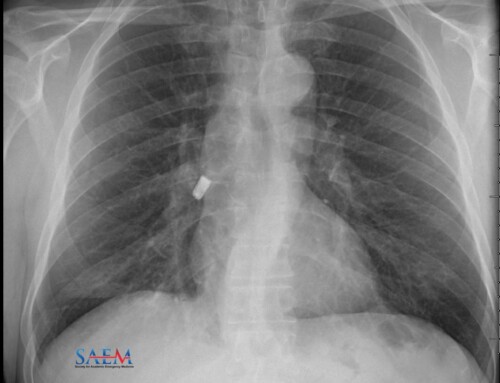

Pneumonia is a common cause for ED visits. How do you decide on whether the patient can be managed as an outpatient or inpatient? To supplement your clinical judgment, many clinicians use the Pneumonia Severity Index (PSI) score.

PV Card: Risk Stratification Scoring Tools in Pneumonia